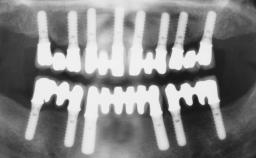

Conventional Loading of Six Implants in the Mandible and Final Restoration with a Full-Arch Metal-Ceramic FDP

A 68-year-old, completely edentulous male patient presented for evaluation and treatment options. He reported excellent general health and was taking no regular medication. He had been edentulous for approximately 12 years, having lost his teeth to periodontal disease and dental caries. The patient’s chief complaint was incompetent function. His secondary concerns included his appearance and the desire for a predictable outcome. He attributed his reduced functional capacity to his lower complete denture, which he described as poor. He was particularly concerned with the denture’s instability and poor fit. In general terms, he was satisfied with the maxillary complete prosthesis. The maxillary prosthesis was characterized by adequate retention, stability, and support, although the fit was considered less than ideal.

# of Implants 6

Type of Implants One-Piece

Defining Characteristics Fully edentulous lower jaw to be rehabilitated with two or more implants

Modality > 4 implants, extending to mental nerve region

Defining Characteristics Fully edentulous lower jaw to be rehabilitated with an implant-borne fixed dental prosthesis

Retention Screw-retained, with 4 or more splinted implants Screw-retained, with 4 or more splinted implants